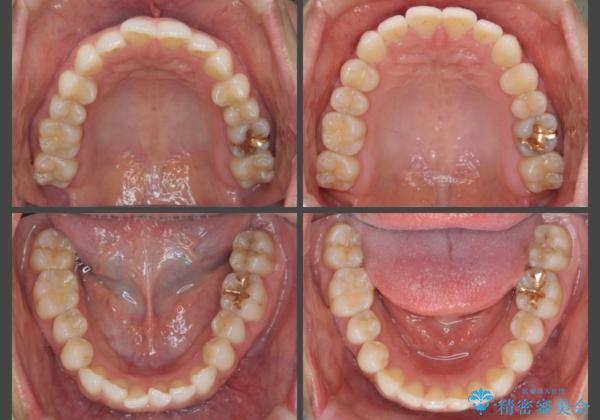

[ インビザライン ] 目立たないマウスピース矯正で、前歯のがたつきをきれいにしたい

- 前歯のがたつきを「装置の目立つワイヤーではなく、マウスピースで治療したい。」と希望され来院されました。

シミュレーションを作成した結果、26枚以下のリーズナブルなモデレートプランが適応であることがわかりました。

費用を抑えられただけでなく、治療期間も約半年と短期間で治療を終了することができました。